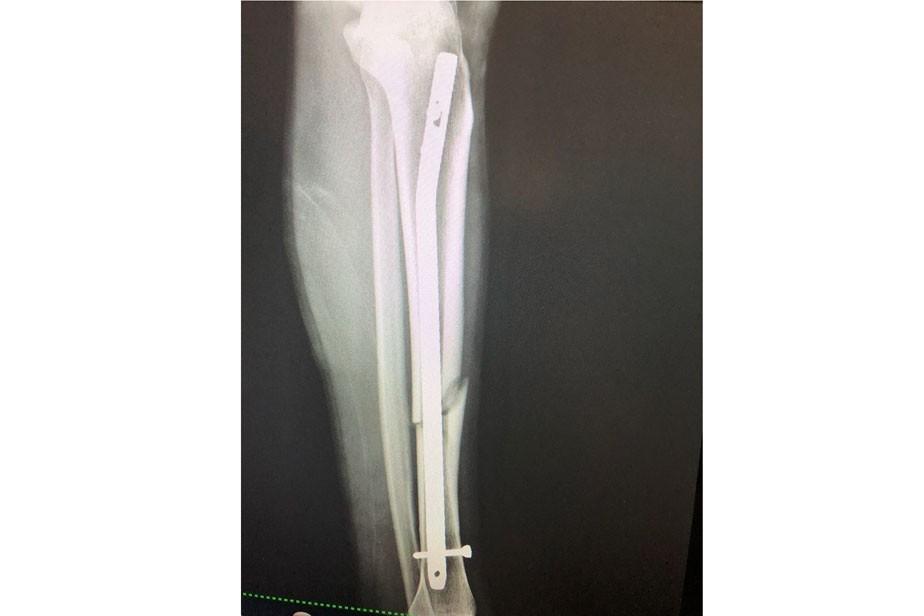

El nuevo dispositivo Arco en C comenzó a utilizarse hoy en la localidad andina, posibilitando la resolución de cirugías traumatológicas complejas.